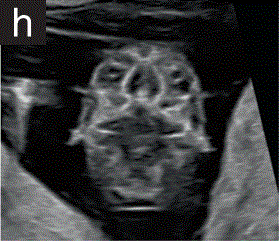

8.脊柱

表2孕11+0至14+0周时可在详细的胎儿扫描中看到的解剖结构(根据需要,在矢状、横断或冠状面切面中)

8.1如果可能的话,应在矢状切面下检查脊柱,评估椎体对齐和皮肤覆盖物的完整性(图2s)。

胎儿mt是什么检查什么疼吗【文献学习/规范指南】ISUOG实践指南(2023更新): 11-14周胎儿超声检查(全文)_https://www.jmylbn.com_新闻资讯_第26张

图2 11+0至14+0周时,可作为详细胎儿超声检查的一部分获得的解剖图。

(s)矢状面图显示胎儿脊柱从颈部到骶骨的长度。注意可见完整的皮肤覆盖物和椎体骨化,这已经开始于骶骨和腰椎和胸椎。

8.2 妊娠12周后,椎体发生骨化。